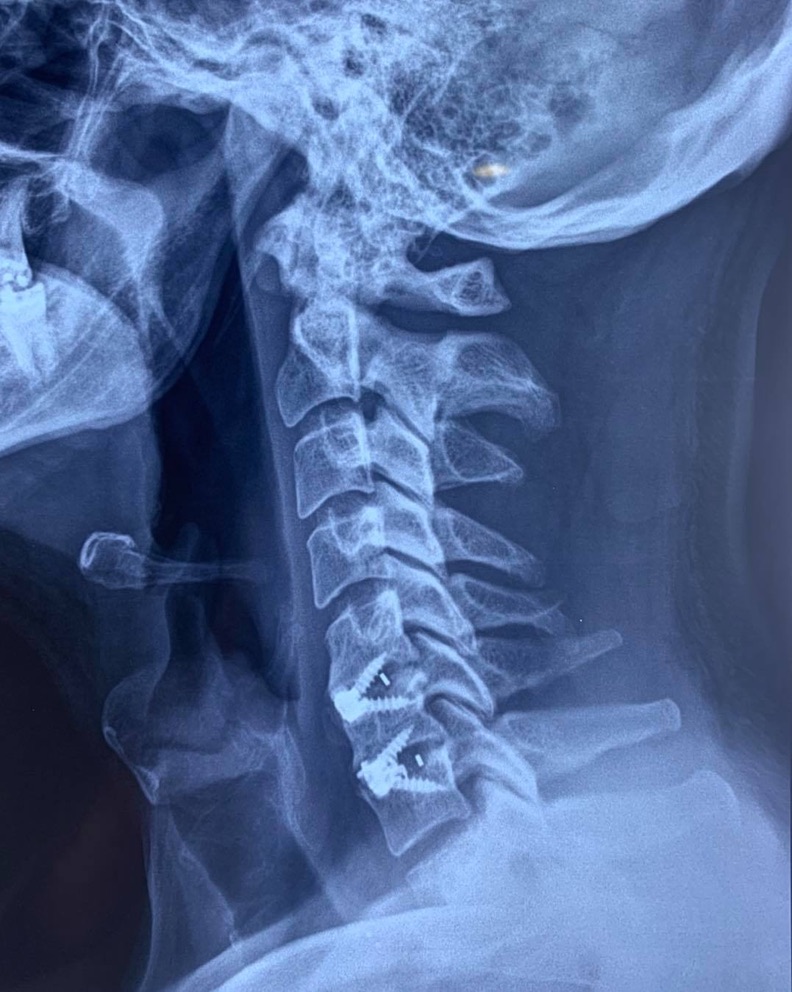

CIRUGIAS

RESULTADOS